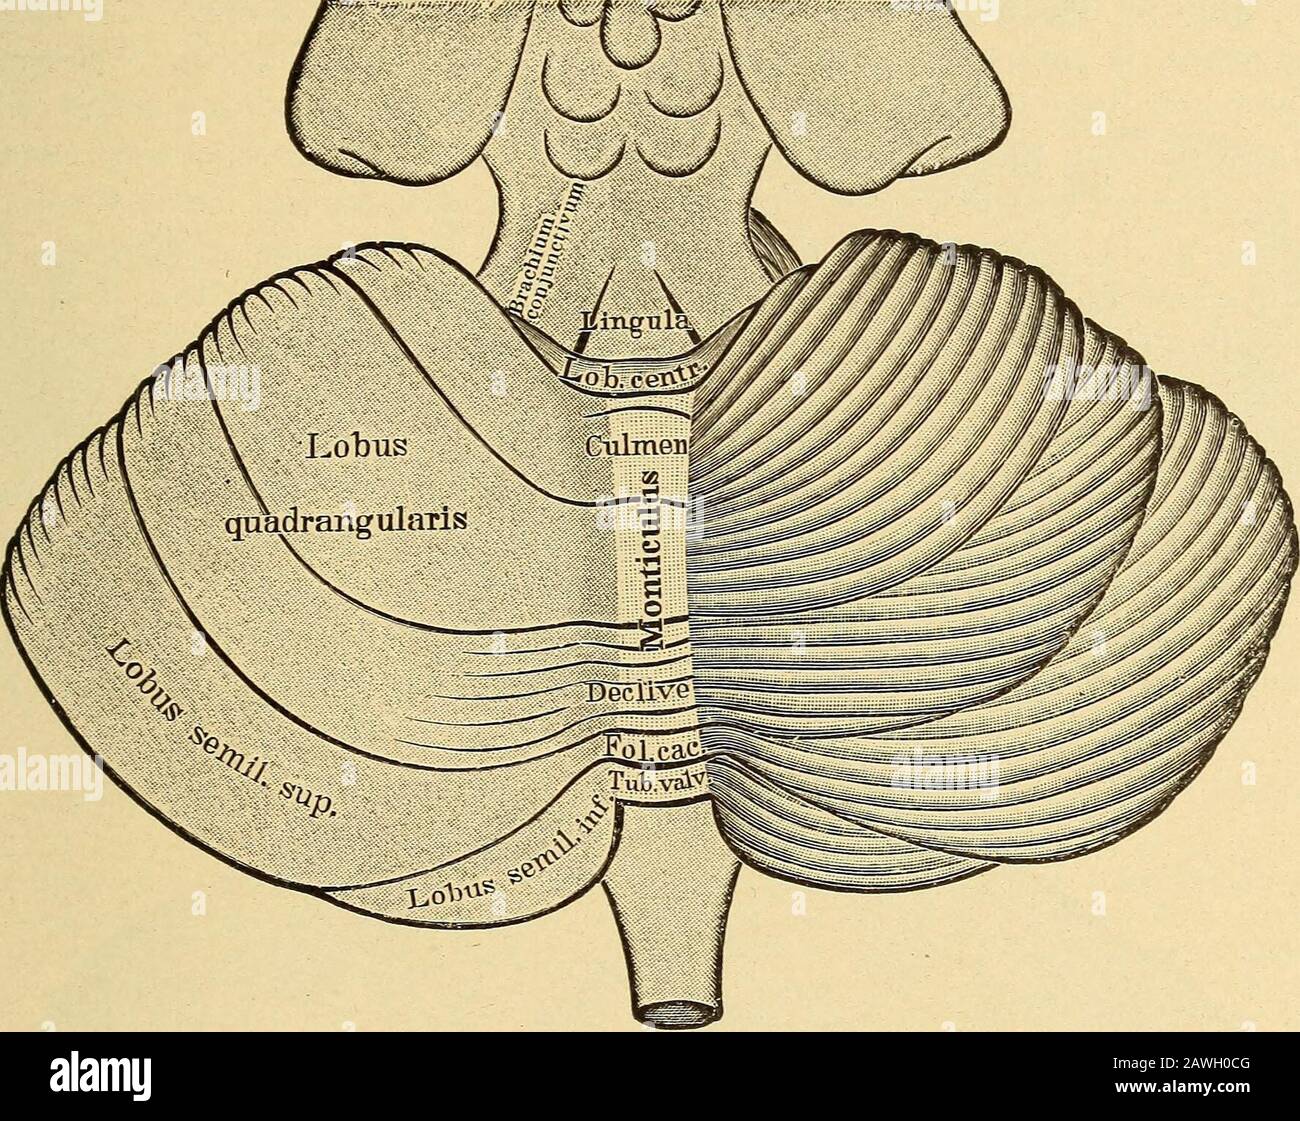

RMRN7XMA–. Anatomie der Katze. Katzen; Säugetiere. 342 NERyOUS SYSTEM. In diesem Teil des Gehirns die Fortsetzung der zentralen Hohlraum ist ein schmaler Kanal, erhält den Namen zerebrale Aquädukt (aqueductus cerebri) oder aquädukt von Sylvius. J. li Abb. 138.-ventrale Oberfläche ov das Gehirn. /-X/I, die zwölf Hirnnerven in Ordnung;/, riechkolben; //, N. opticus; ///, N. Augenmotorischen;/W, N. trochlearis; F, N. trigeminus (I, mandibularnerv; 2, maxillaris Nerv; 3, augenärztliche Nerv; 4, sensorische Wurzel); F/, N. abducens; 17/, N. facialis; 17//, N.; acuslicus LY, N. glossopharyngeus; X, N. vagus; EIN'/, N. acce

RM2AWH0CG–Erkrankungen des Nervensystems .. . Abb. 13.-Diagramm des Gehirns, Der Pedonkel. (Nach Obersteiner.) Qa, Anterior corpora quaderigemina; AS, Aquädukt von Sylvius; FU:, pos-terior longitudinal Bundle; Tg, teg-mentum; Nt, roter Zellkern; SnS, substantia nigra soemmeringi; 1, frontalpontal Trakt; 2, Trakt des Motors. Kraniale Nerven; S, Hirngewebe, Hirngewebe, Hirngewebe, Hirngewebe, Hirngewebe, 5. 6, Bündel vom lem-niscus zum Fuß; 7, Stratum intermediimi. Die makroskopische ANATOMIE DES ZENTRALEN NERVENSYSTEMS 21 Rior Eminence im Menschen ist excleclingiy klein c